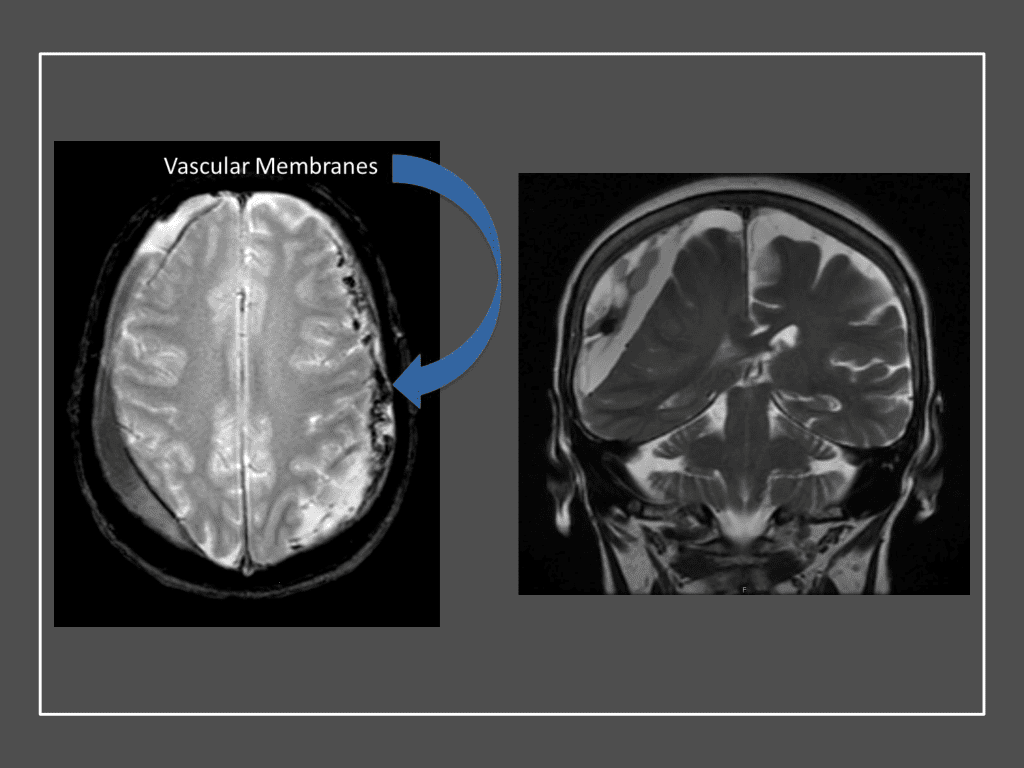

Figure 7. Neovascularized membranes within cSDH

Although conventional surgical methods, such as burr hole irrigation or observation in asymptomatic or minimally symptomatic patients have been the mainstay of treatment, middle meningeal artery (MMA) embolization has emerged as a promising adjunctive or alternative treatment. MMA embolization is a neuroendovascular technique which involves placing a microcatheter into the Middle Meningeal Artery, most commonly on the side of the cSDH (occasionally, bilateral embolization has been recommended for larger or bilateral collection. Embolization of both the anterior (frontal) and posterior (parietal) division is performed using a variety of embolic materials (liquid NBCA, Onyx, coils), although polyvinyl alcohol particles of <250 microns are most commonly used to achieve distal penetration and occlusion of the pre-capillary and capillary beds. The micro-leakage of blood and transudative proteinaceous inflammatory fluid in these inflammatory membranes is creating an imbalance in cycle of resorption and preventing resolution or promoting recurrence or growth of these cSDH collections and associated mass effect and midline shift.

Figure 8. Dense contrast staining of vascular membranes during embolization.